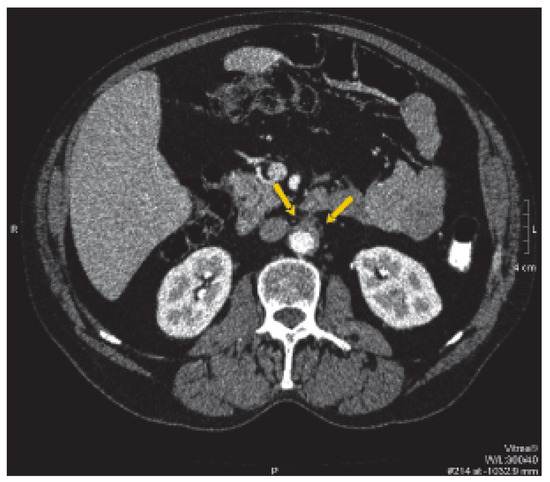

M. Ormond (retroperitoneale Fibrose)

by Y. Suter, A. Cornelius and D. Conen

Ein 49jähriger Patient stellte sich mit seit zwei Monaten anhaltenden rezidivierenden kolikartigen Oberbauchschmerzen vor. Es wurde bei Cholezystolithiasis eine Cholezystektomie durchgeführt. Während der Hospitalisation fiel eine Erhöhung der Transaminasen ohne sonographisches Korrelat auf. Eine postoperative Computertomographie des Abdomens liess ein retroperitoneales Hämatom vermuten [...] Read more.

Ein 49jähriger Patient stellte sich mit seit zwei Monaten anhaltenden rezidivierenden kolikartigen Oberbauchschmerzen vor. Es wurde bei Cholezystolithiasis eine Cholezystektomie durchgeführt. Während der Hospitalisation fiel eine Erhöhung der Transaminasen ohne sonographisches Korrelat auf. Eine postoperative Computertomographie des Abdomens liess ein retroperitoneales Hämatom vermuten (Abb. 1). [...] Full article